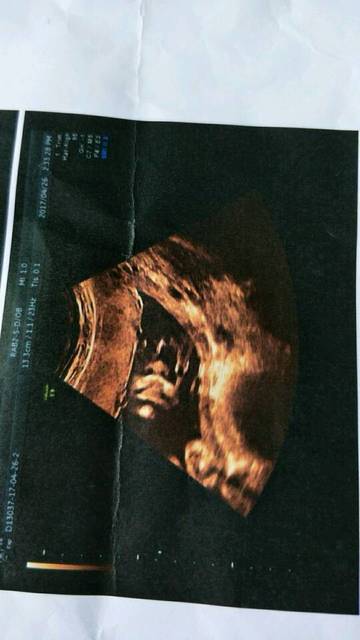

四维顺利通过,宝贝侧脸照_二十八周查的四维,